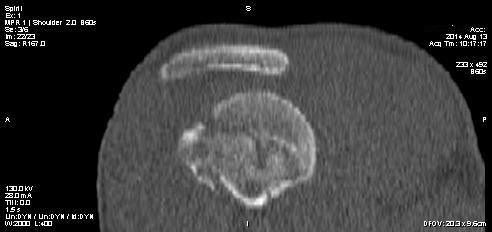

Уважаемые коллеги! 12.08.2014 поступил молодой человек 28 л. спортивного сложения (активно занимается "железом") - травма уличная - получил удар током 220В от электронасоса, затем, по всей видимости, упал на правое плечо (изначально факт падения не озвучивался). В связи с электротравмой и срывом ритма госпитализирован в ОАИТ. По стабилизации состояния начал жаловаться на интенсивные боли в правом плечевом суставе. Выполнена Р-графия правого плечевого сустава, дежурный травматолог расценил видимый костный фрагмент как отрывной перелом либо головки, либо суставного отростка лопатки; иммобилизация правой верхней конечности осуществлена бандажом. На следующий день боли в правом плечевом суставе сохранялись, осмотрен клинически - заподозрен задний вывих плеча, на повторной прямой Р-грамме ничего существенного, снимок с выведением большого бугорка не удался из-за ограничения наружной ротации. Затем выполнена КТ - диагностирован переломо-вывих правого плеча. Под общим обезболиванием вывих закрыто устранен, иммобилизация осуществлена гипсовой повязкой. Возникает вопрос: что делать дальше? Необходимость оперативного вмешательства вроде бы  очевидна, но вот его объем?  Пока планируется элевация импактированного фрагмента, остеосинтез всего этого на PHILoSе. Второе мнение - синтез фрагмента головки и малого бугорка винтами (Герберта?), фиксация большого бугорка (подшивание). Либо сочетание этих способов... Время вроде бы поджимает, хотелось бы узнать видение ситуации уважаемым сообществом.